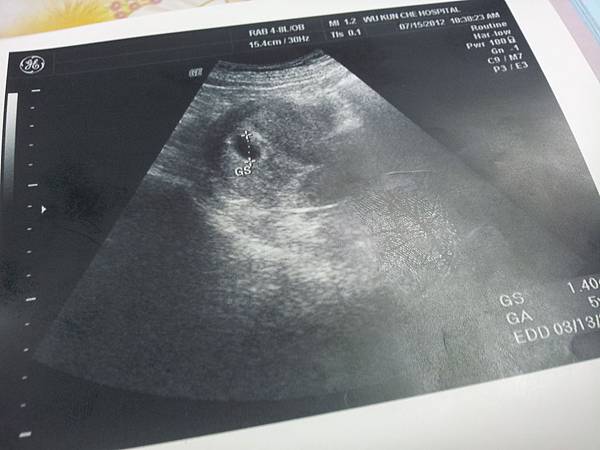

最後,先選了高雄老口碑的『吳昆哲』看診

吳昆哲位在民權二路上,可能因為看診時間是星期日,所以醫院裡的病患非常非常的多,雖有專屬停車場(付費),但還是要等一陣子

醫生說胚胎還非常非常的小,但是應該有著床了,保險起見隔周要再來看一次

預產期2013/03/13雙魚座.........

2012。07。15

第一張照片